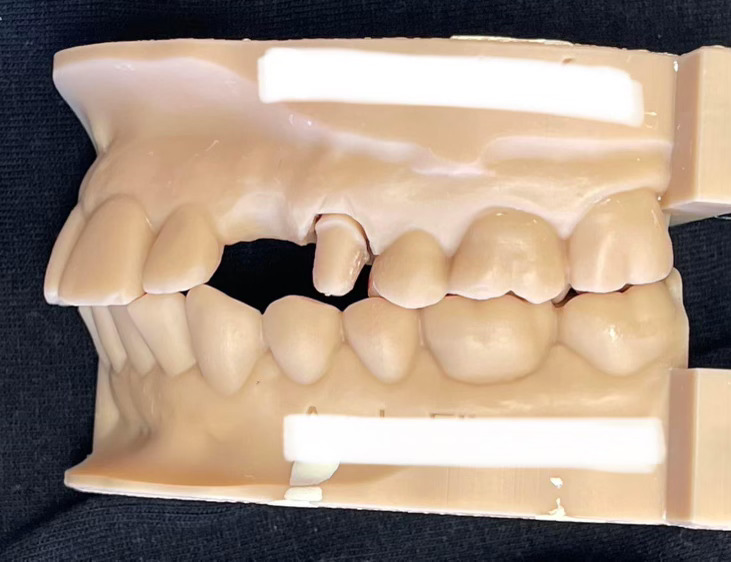

Case Study: Dental Implant

A patient with a missing tooth received a dental implant, restoring both function and aesthetics.